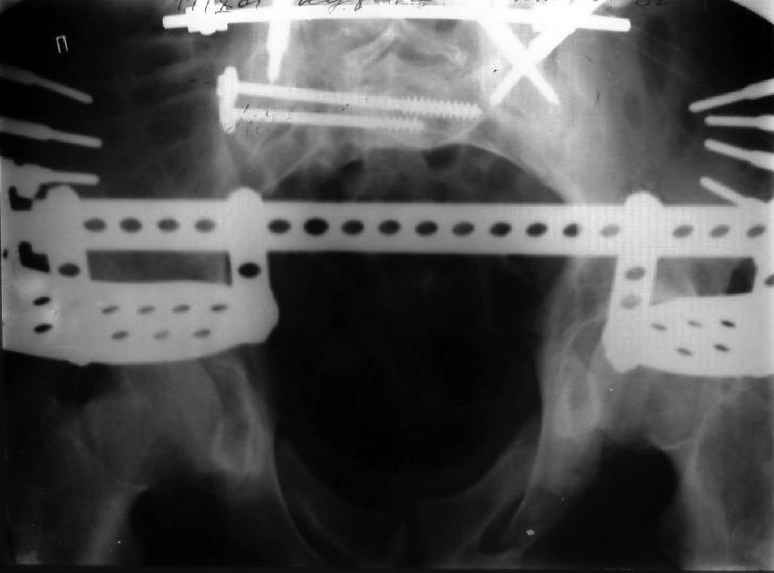

Мы, как правило, в подобных случаях проводим оперативное лечение в несколько этапов. Первым устраняем деформацию при помощи АВФ (кольцевой конструкции с фиксацией задних отделов), вторым- выполняем введение илиосакралых винтов, накостный остеосинтез передних отделов.

План, конечно, очень общий, возможны варианты.

Для информации к размышлению о возможности исправления имеющейся деформации предлагаю похожий случай.